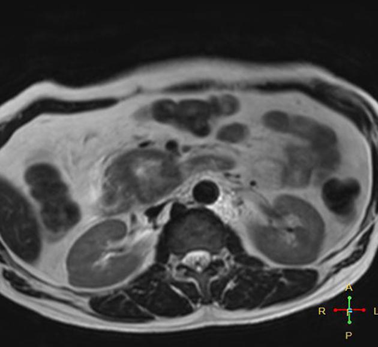

Case 1: Early Detection in New-Onset Diabetes

A 62-year-old male consulted his doctor with newly diagnosed diabetes and a recent 4 kg weight loss. Although he experienced mild, persistent epigastric discomfort, he showed no signs of jaundice. Lab tests showed elevated blood sugar but normal liver function. Due to his symptoms, a contrast-enhanced CT scan was done, revealing a 2.5 cm mass in the pancreatic head. This finding was confirmed via endoscopic ultrasound and biopsy, which identified it as pancreatic ductal adenocarcinoma. The patient underwent a Whipple procedure (pancreaticoduodenectomy) and received adjuvant chemotherapy with gemcitabine. Three years post-treatment, he remained free of disease. This case highlights the importance of investigating new-onset diabetes in older adults as a possible early sign of pancreatic cancer.[164]

Figure 3 Coronal C+ portal venous phase